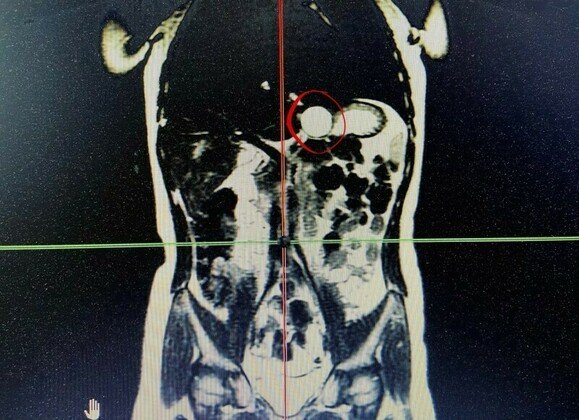

Как рассказали в РДКБ, у девочки диагностировали кистозное удвоение желудка — редкую патологию, при которой формируется полость, не связанная с основным органом. Образование диаметром около 3 см располагалось в зоне перехода желудка в пищевод и грозило воспалением.